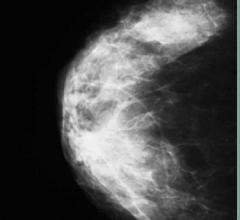

Breast density, or fibroglandular density, is found through breast imaging and compares the amount of fat to the amount of tissue.

Dense breast tissue can mask the appearance of tumors and limit the performance of mammography. When used as an adjunct ...

Digital breast tomosynthesis (DBT), or 3-D mammography, is an advanced mammography that uses low-dose X-rays to detect ...